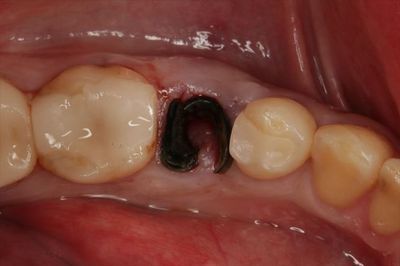

実際の左下第二小臼歯の状態です。

とても黒く変色しています。